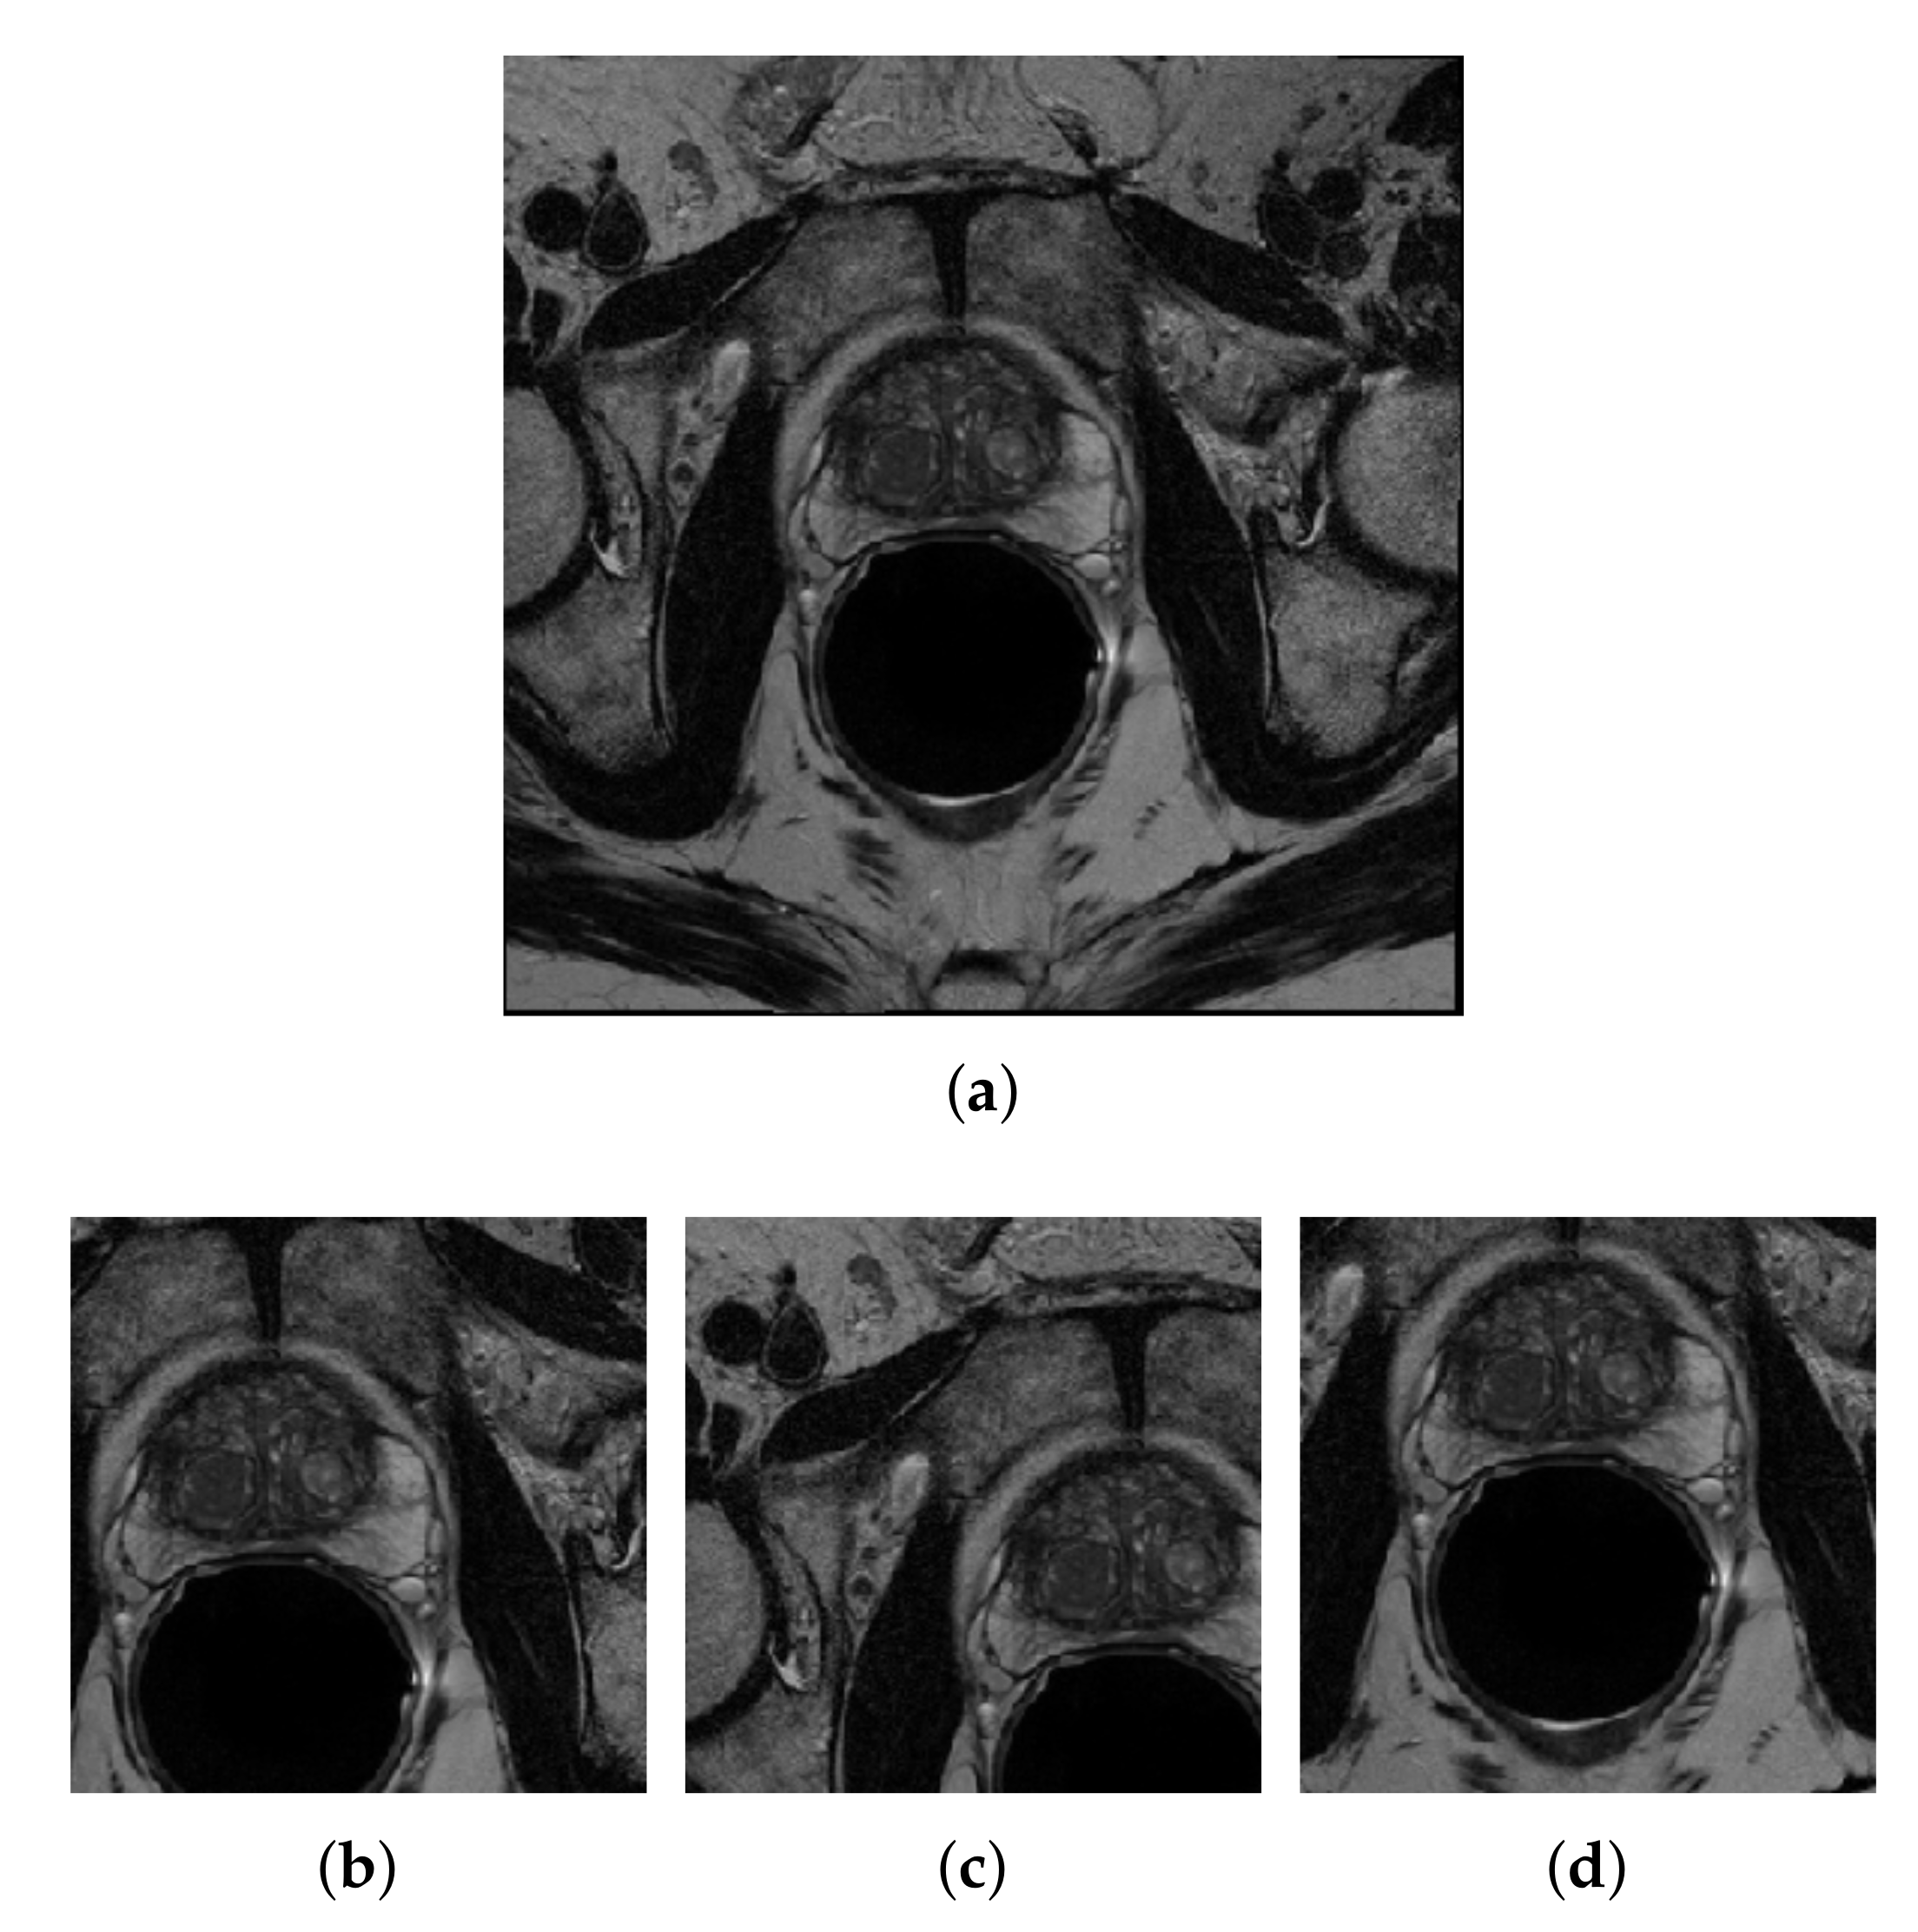

3.3. Image Pre-Processing

3.3.2. Center-Cropping